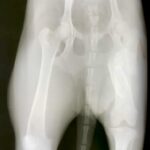

Sweet lovely Maisey is just under a year old. She was hit by a car and suffered a fractured femur. Unfortunately, she either didn’t have owners, or if she did, they didn’t bother to take her to a veterinarian to be treated. So Maisey’s body healed all on it’s own, leaving her right femur shorter than her left.

Maisey is fully grown and weighs just under 25 lbs. She has a soft, slightly shaggy mid-length coat, and is not a heavy shedder. She gets around fine on her healed leg. Aside from a slight hitch in her gait she runs and plays as though she was never injured. Maisey is spayed, fully vaccinated and in great health.